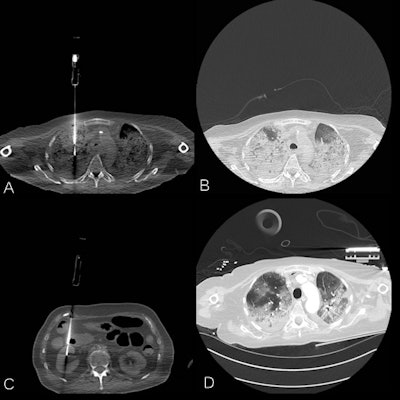

A series of annotated CT images of COVID-19 patients. A: Postmortem lung biopsy, same region as premortem CT image. B: Postmortem lung window, same region as premortem CT image. C: Postmortem renal biopsy. D: Premortem CT, 24 hours before biopsies. Courtesy of Dr. Jan Vanrusselt.

A series of annotated CT images of COVID-19 patients. A: Postmortem lung biopsy, same region as premortem CT image. B: Postmortem lung window, same region as premortem CT image. C: Postmortem renal biopsy. D: Premortem CT, 24 hours before biopsies. Courtesy of Dr. Jan Vanrusselt.Two clinicians, two radiologists, two microbiologists, and two pathologists independently assessed the clinical file, the postmortem CT scan, microbiology findings, and histology slides respectively. The clinical cause of death and contributing diagnoses were abstracted from the discharge letter. During a multidisciplinary meeting, the multiple causes of death and contributing diagnoses were formulated and compared to the certificate of cause of death and contributing diagnoses.